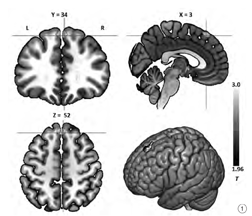

对比对照组,网瘾组内侧前额叶[团块大小=50体素;峰值点坐标(MNI空间):x=3,y=33,z=57)]显示增强的VMHC(VMHC值:网瘾组=0.45,对照组= 0.29,T=4.32,P<0.001),见图1。